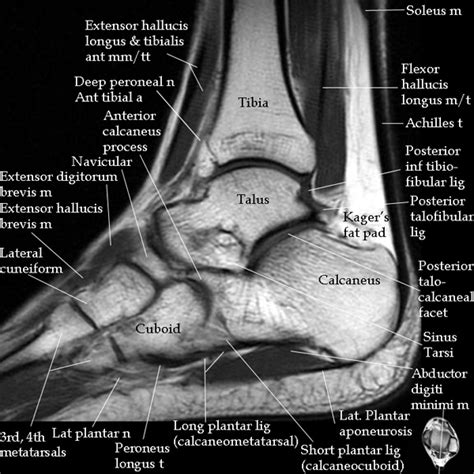

Alright, let’s get down to the basics of ankle taping for football . Before we jump into the specific techniques, it’s important to understand the different types of tape and the general principles behind the process. First off, you need to know the right materials. The most common type of tape used for ankle taping is athletic tape . This tape is specifically designed to adhere well to the skin while still allowing for some flexibility and movement. It’s usually made of a cotton or rayon material with a strong adhesive backing. The width of the tape typically used is 1.5 inches, but you might also find narrower or wider options depending on the specific taping technique. Another important material is pre-wrap , or underwrap. This is a thin, foam-like material that goes directly on the skin before the athletic tape is applied. Pre-wrap serves a few key purposes. Firstly, it protects the skin from the adhesive in the athletic tape, which can cause irritation or blisters, especially with repeated taping. Secondly, it provides a base layer for the tape to adhere to, creating a more secure and comfortable taping job. It’s also crucial to have scissors on hand, preferably athletic tape scissors, which have a rounded tip to avoid cutting the skin. Finally, you’ll need some knowledge of the anatomy of the ankle. Knowing the location of the ligaments, tendons, and bones is essential for effective taping. This helps you understand where to apply the tape for optimal support and protection. This means getting to know the lateral ligaments (on the outside), the medial ligaments (on the inside), and the tendons that run around the ankle. A basic understanding of these structures ensures that the taping technique is targeted and effective. Then comes the taping technique itself. Generally, the process involves a series of steps designed to support the ankle and limit unwanted movement. This usually involves applying anchors, stirrups, horseshoes, and figure-eight wraps, each serving a specific purpose in stabilizing the joint. Anchors are the base layers of tape, providing a foundation for the other wraps. Stirrups are strips of tape that run from the inside of the ankle, under the heel, and up the outside. Horseshoes wrap around the ankle, providing additional support, and figure-eight wraps help to further stabilize the joint. Each step is carefully executed, and the order is important to maximize the tape’s effectiveness.